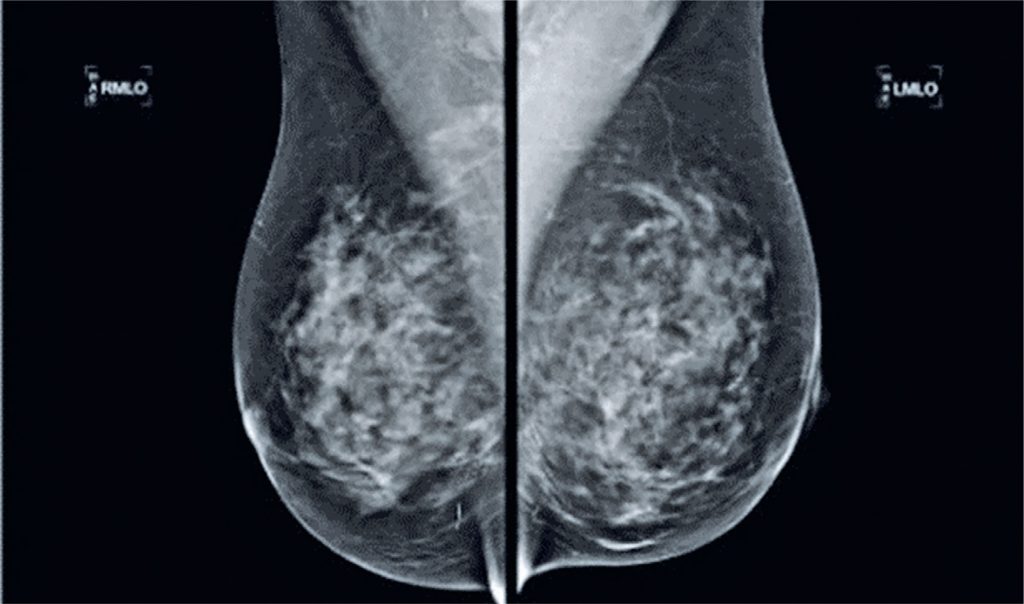

This case report discusses the migration of a foreign body from the breast to the mediastinum, which is rarely reported, and highlights complications associated with Okibari acupuncture. This technique involves the insertion of metal fragments into the skin. A 53-year-old woman underwent mammography showing acupuncture-related metallic fragments in the breast. Cardiac evaluation revealed the presence of metallic fragments in the right ventricle and myocardium. Despite the fragments‘ location in the mediastinum, the patient remained asymptomatic, leading us to take a conservative approach. This case highlights the importance of awareness of the potential complications of foreign bodies and emphasizes the need for careful monitoring.